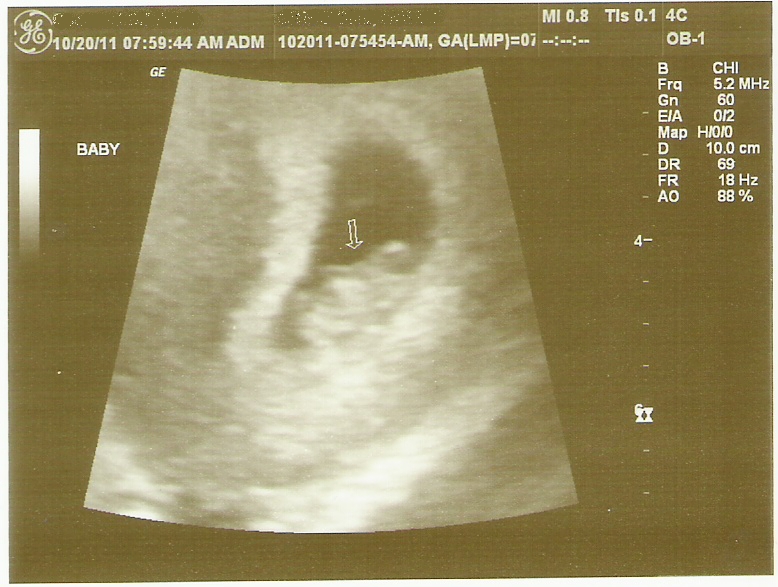

Their first grandchild!

I'm 10 weeks today and I'm due June 1st; 11 days before their 30th wedding anniversary. And

considering I was 23 days late, I think the odds are in favor of this baby

being late too (but we'll see, you never know). So s/he may be born right

around their anniversary. Side note: I got my BFP the day Sarina was born.

I literally gasped and put my hands over my mouth when I saw the u/s picture. I'm THRILLED for you and Mark!! Congrats and a super H&H 9 months to you!!!

So yes, I knew at the GTG but I wasn't ready to tell yet. I didn't have my first appointment until the next week and because I was having like no symptoms other than bloating I was really nervous about seeing an empty sac. But the tech found the heartbeat immediately (at 166bpm)!